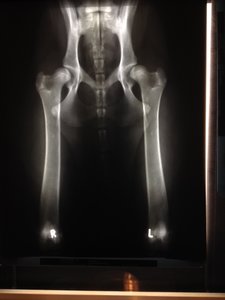

Abby humpelt und hinkt nach wie vor, keine wirkliche Verbesserung zu erkennen. Ich hab echt Schiss, dass sie durch ihre bescheuerten Aktionen die Schrauben gelockert hat (ich bin normalerweise nicht so schwarzmalerisch veranlagt) Ich muss sie 8 Stufen hoch und runter tragen, wenn wir Gassi gehen (40kg :shock